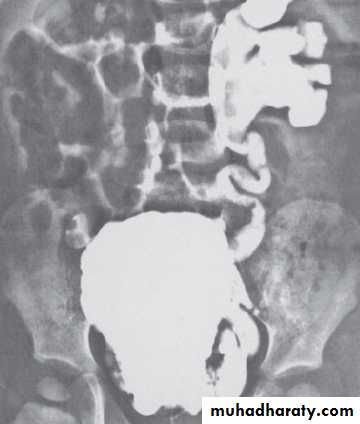

U.S. , IVU, MCUG( it shows the valve folds, the trabeculated bladder with diverticulae & even vesicoureteral reflux).

Cystourethroscopy confirm the Dx.